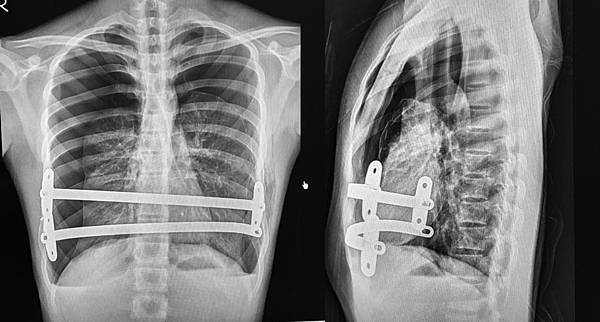

這項技術的原理是在肋骨間置入一矯正板,利用外側的下方肋骨支撐起內側的上方肋骨。原理簡單,但變化很大,如肋間的選擇,矯正板長度及弧度的變化, 固定方式等等,使得每位醫師做的方法都不同,更造成了經驗多與少的差別。

納氏手術的演進